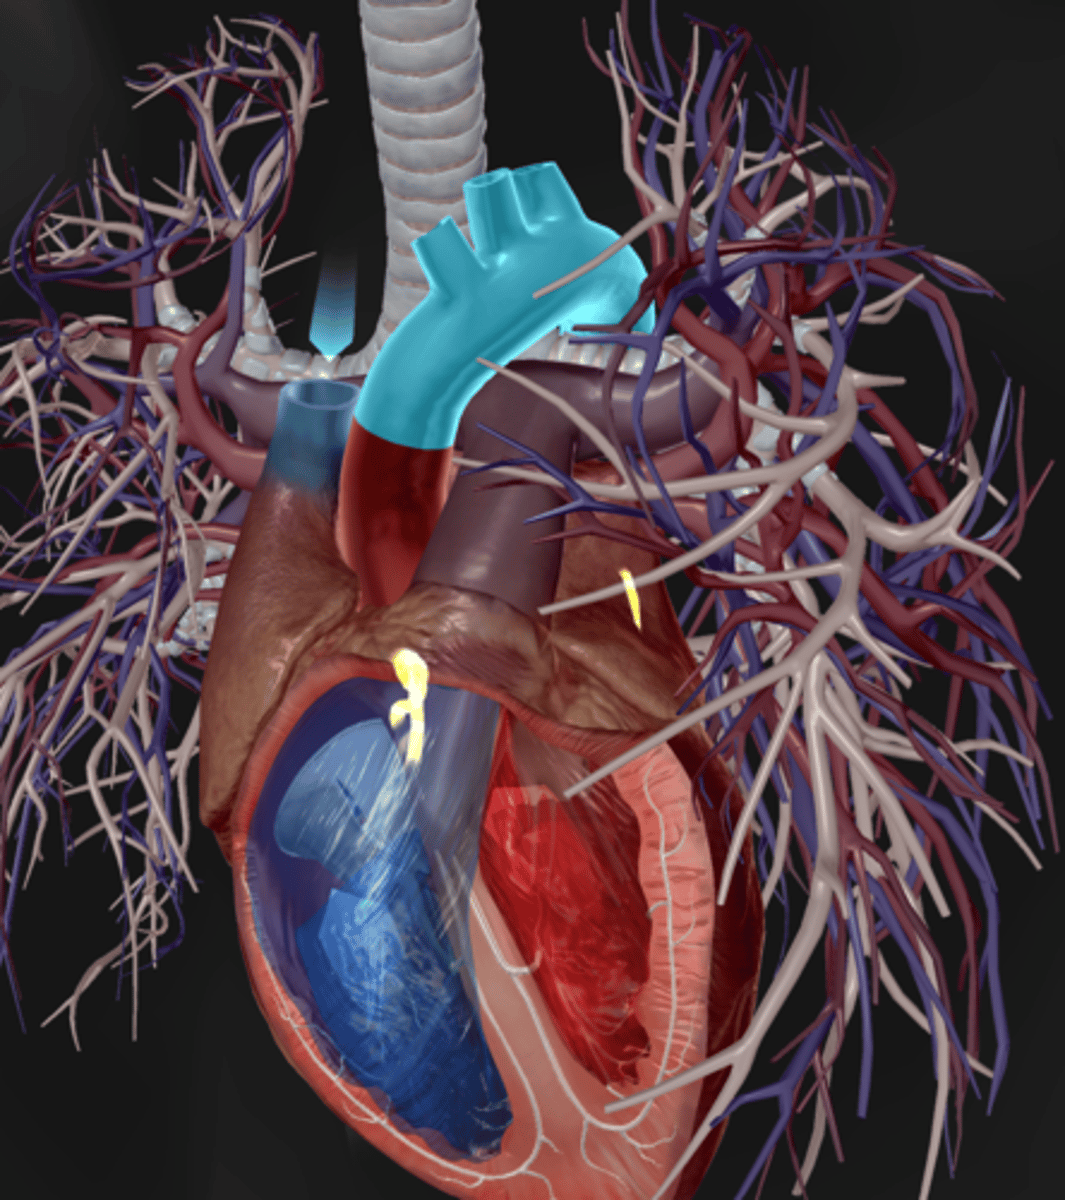

Pulmonary arteries

Pulmonary veins

Pulmonary trunk

Aortic arch